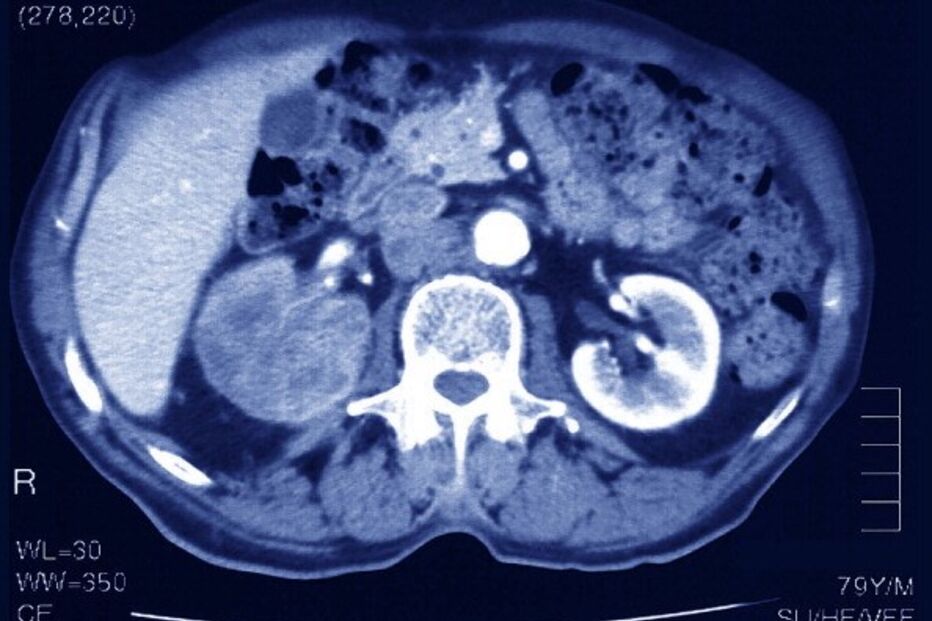

Cancro do Rim: Saiba tudo sobre este carcinoma

O cancro do rim foi o 18.º cancro mais frequente em Portugal em 2020. De acordo com os últimos dados, em 2018 foram diagnosticados 1301 novos casos e 507 óbitos relacionados à doença, cerca de 1,8% de todas as mortes por cancro em Portugal.